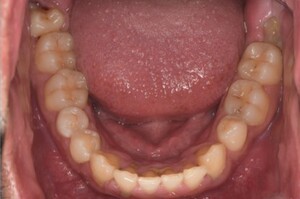

健康な歯ぐきの特徴

健康な歯ぐきは、綺麗なサーモンピンク色で、歯と歯の間が三角形でうまっています。近くで見ると、表面にみかんの皮のような細かなつぶつぶがあります。痛くない程度の力で歯ブラシの毛先を歯ぐきに当てて磨いてみましょう。出血が起こらなければ、健康な状態だといえます。

健康な状態の歯ぐきの写真